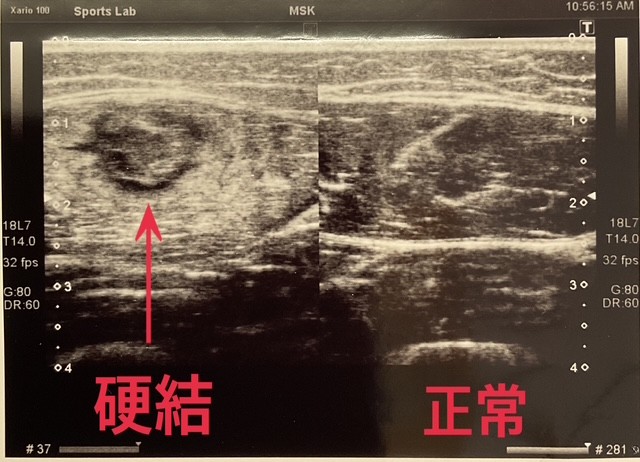

肉離れを繰り返す原因その2は

硬結(こうけつ)です。

肉離れをすると

修復過程で硬結と呼ばれる

瘢痕(はんこん)組織が形成されます。

(エコー画像)

瘢痕組織は体内に出来るかさぶたのようなもので

コラーゲン線維も細く柔らかく

本来の太く強靭で張力に耐えるコラーゲン線維とは

違うものになります。

そして線維の方向もぐちゃぐちゃになっています。

細胞も筋細胞ではなく線維芽細胞から形成されており、

本来の筋肉と瘢痕組織では

固さや強度などが異なります。